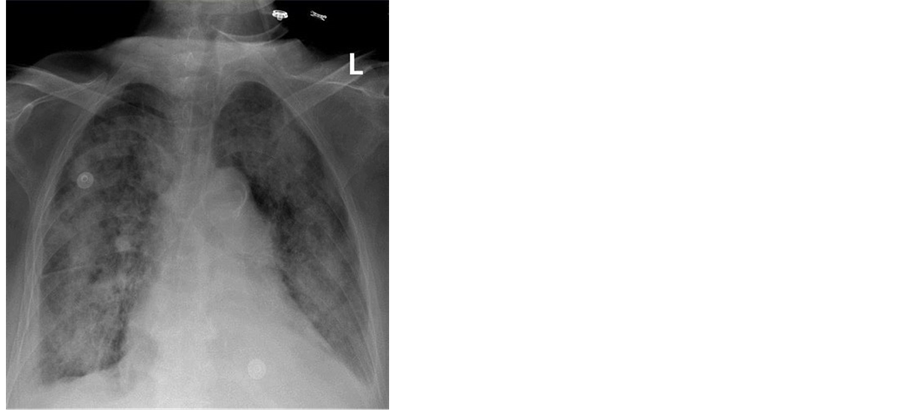

Two days after admission; diffuse alveolar infiltrates developed (Figure 2). Patient was transferred to the Intensive Care Unit (ICU) and placed on mechanical ventilator support. Patient was treated as a case of adult respiratory distress syndrome (ARDS). Trans echocardiography was done and revealed no abnormalities.

Figure 2. Portable chest x-ray two days after admission. Diffuse bilateral alveolar infiltrates.